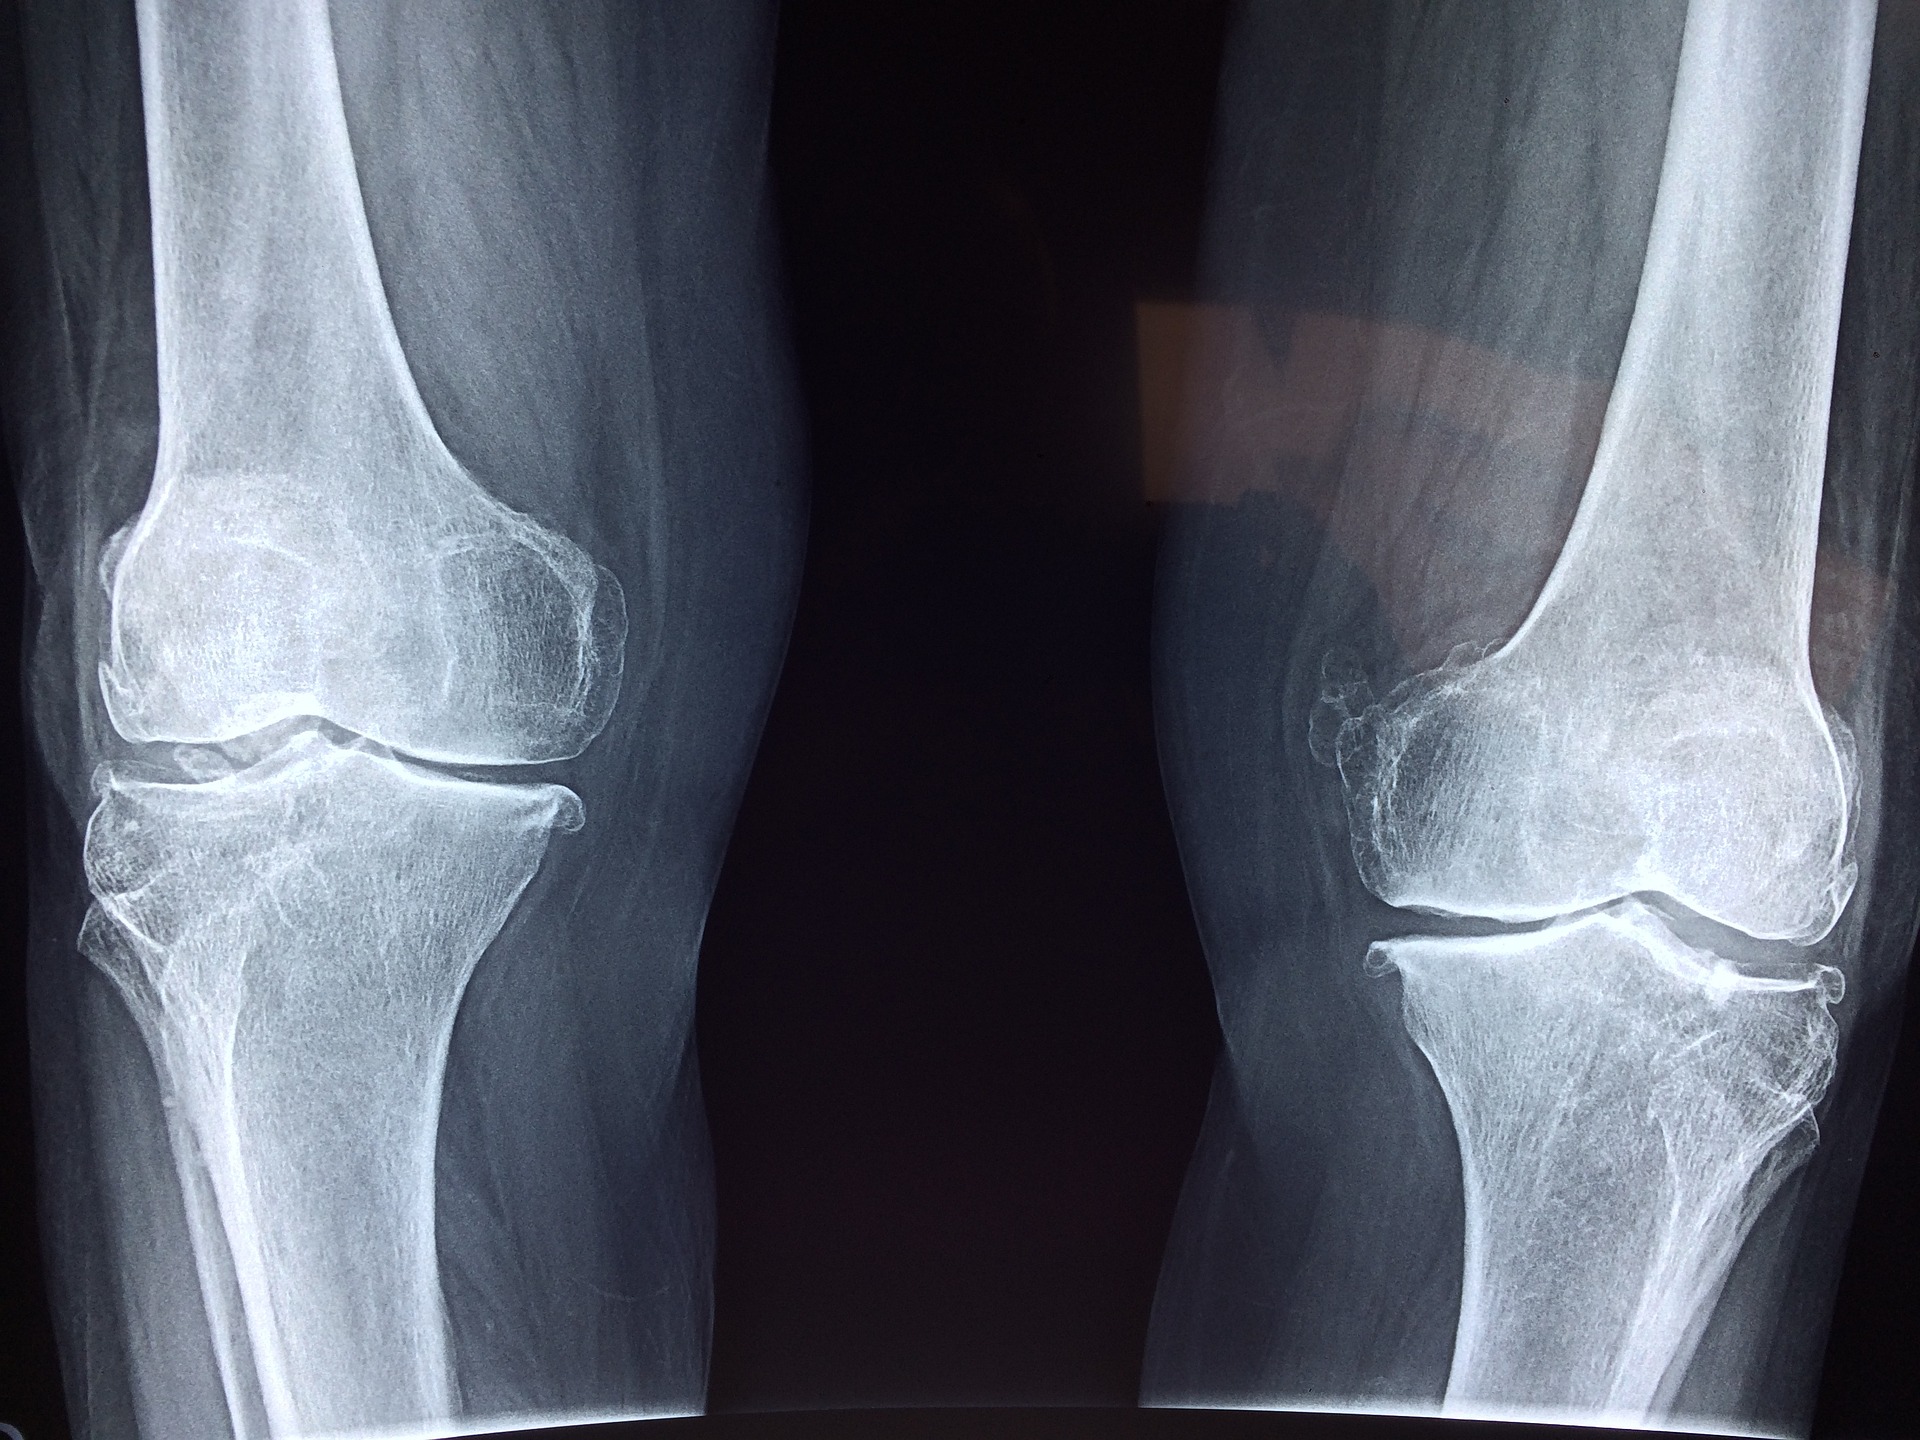

퇴행성관절염은 관절염 중 가장 흔한 형태 중 하나입니다.

관절염은 관절의 염증으로 인해 발생하는 질환으로, 퇴행성관절염은 연령과 운동의 강도에 따라서 차등적으로 발생할 수

있습니다.

퇴행성관절염은 일반적으로 손목, 손가락, 무릎, 엉덩이, 등과 같은 관절에서 발생합니다.

이러한 관절들은 연골로 덮여 있으며, 연골은 관절이 부드럽게 동작할 수 있도록 해줍니다.

그러나 퇴행성관절염은 연골의 파괴로 인해 관절이 더 이상 부드럽게 동작하지 않고, 관절 퇴행을 일으키며 관절통,

강직, 염증 등의 증상을 유발합니다.